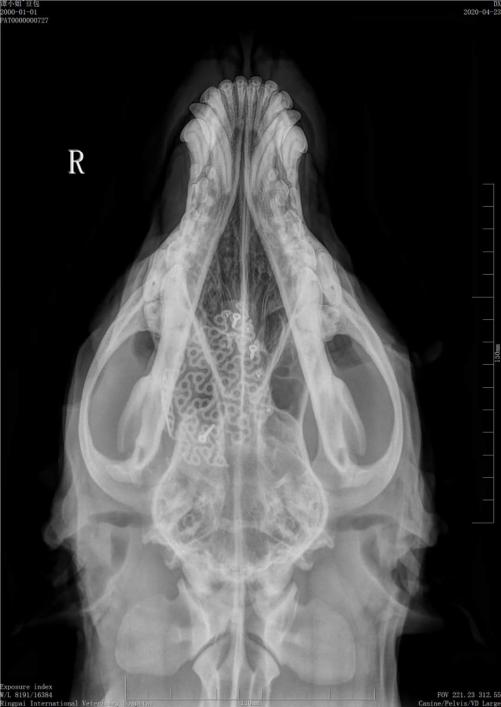

术后影像